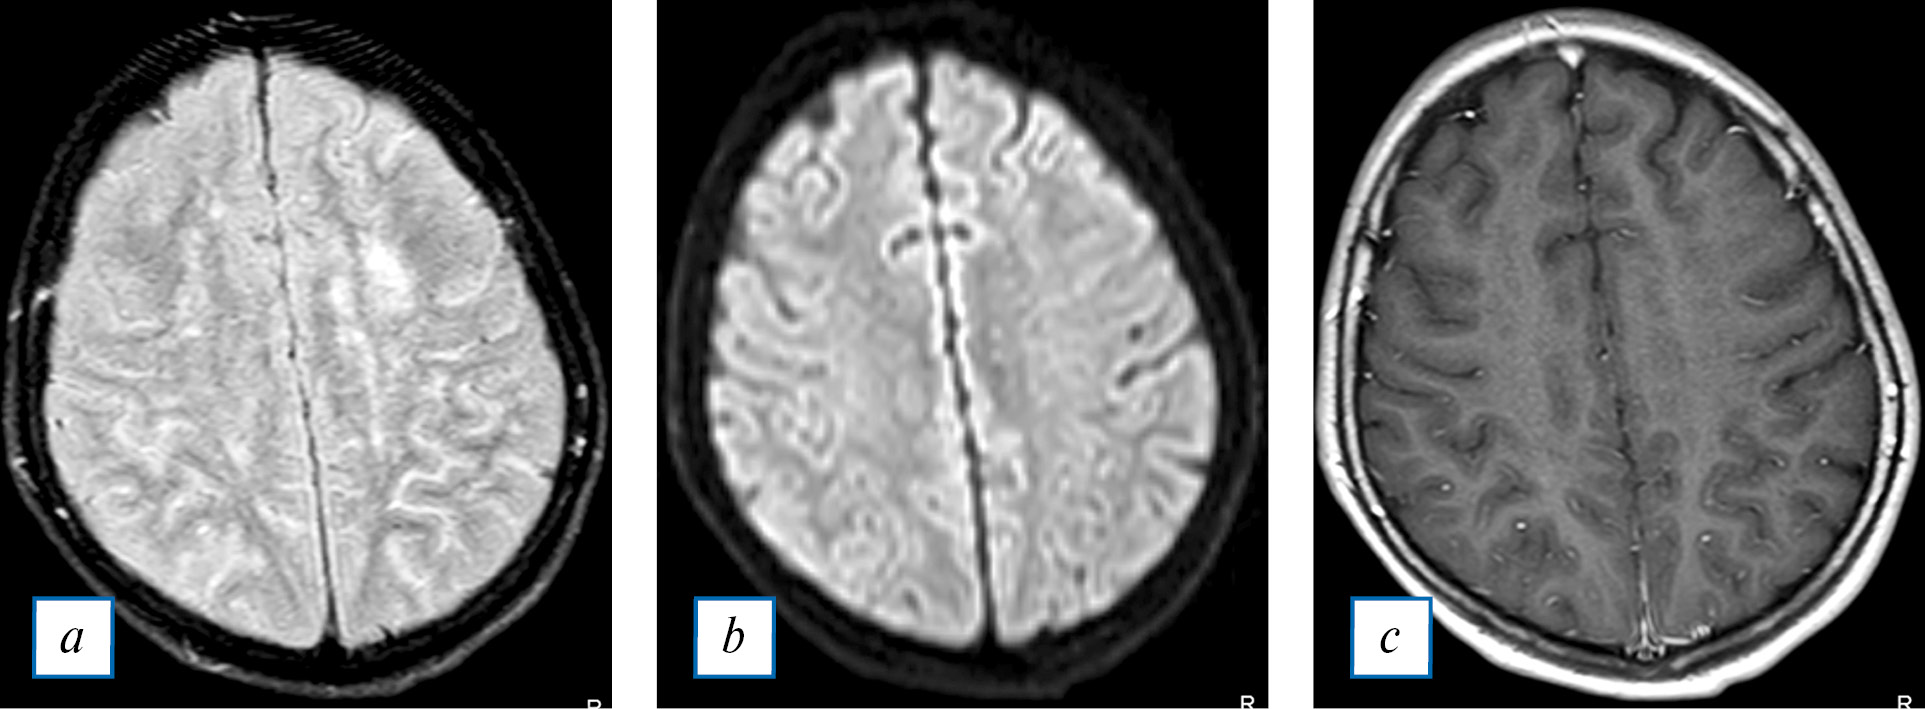

Рис. 3. МРТ головного мозга ребенка с клинически подтвержденным бактериальным эндокардитом (обведено красным): a — FLAIR (абсцесс в левой затылочной доле); b — карта измеряемого коэффициента диффузии (ограничение диффузии от содержимого абсцесса); с — Т1-ВИ с внутривенным контрастированием (накопление контрастного препарата стенкой абсцесса).

Fig. 3. Brain MRI of a child with clinically confirmed bacterial endocarditis: a — FLAIR (abscess in the left occipital lobe); b — ADC mape (restriction of diffusion from the contents of the abscess); с — T1-weighted brain MRI with contrast (contrast enhancement in the abscess wall).